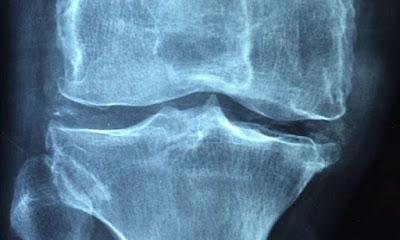

Sin embargo, la prueba clave para una posible nueva terapia es su capacidad para atacar el proceso de reparación natural que se ve comprometido por la edad o una enfermedad inflamatoria. Los investigadores demostraron que administrar PEPITEM adicional limita la pérdida ósea y mejora la densidad ósea en modelos animales de menopausia, que es un desencadenante común de la pérdida ósea osteoporótica en humanos. Sus estudios también mostraron hallazgos similares en modelos de enfermedad ósea inflamatoria (artritis), donde PEPITEM redujo significativamente el daño y la erosión ósea.

Estos hallazgos fueron subrayados por estudios que utilizaron tejido óseo humano, extraído de pacientes mayores durante una cirugía articular. Estos estudios demostraron que las células de personas mayores responden a PEPITEM, aumentando significativamente la maduración de los osteoblastos y su capacidad para producir y mineralizar tejidos óseos.